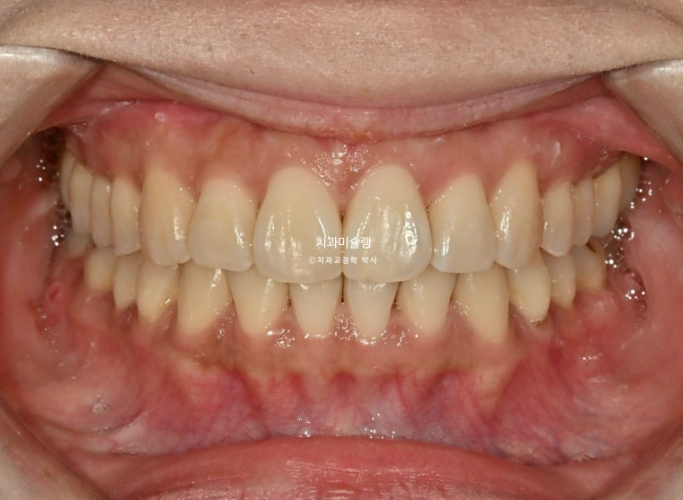

두번의 재제작을 통해 정확히 맞아진 중심선

어금니 교합은 물샐틈 없는 1급 교합관계를 보입니다.

이제 전후 비교 보겠습니다.

23.08~25.11

총 치료기간은 2년 3개월이고 재제작 2회입니다.

현재는 비베라를 매일 잘 때만 끼면서 결과 유지중입니다.

뻗친 앞니 개선으로 깔끔한 미소가 되었습니다.

돌출입은 비발치 치료로 과하지 않게 적당히 개선이 되었습니다.